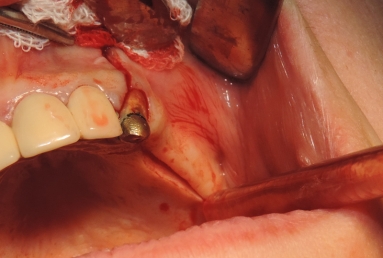

Final situation: an external sinus lifting procedure was performed. The sinus membrane was lifted off the sinus walls and new bone was applied in the vertical space created ( Bio Oss- switzerland- bovine origin). After 6 months, while the new bone is integrated in the maxillary bone of the patient, dental implants can be applied. the case is still during treatment.